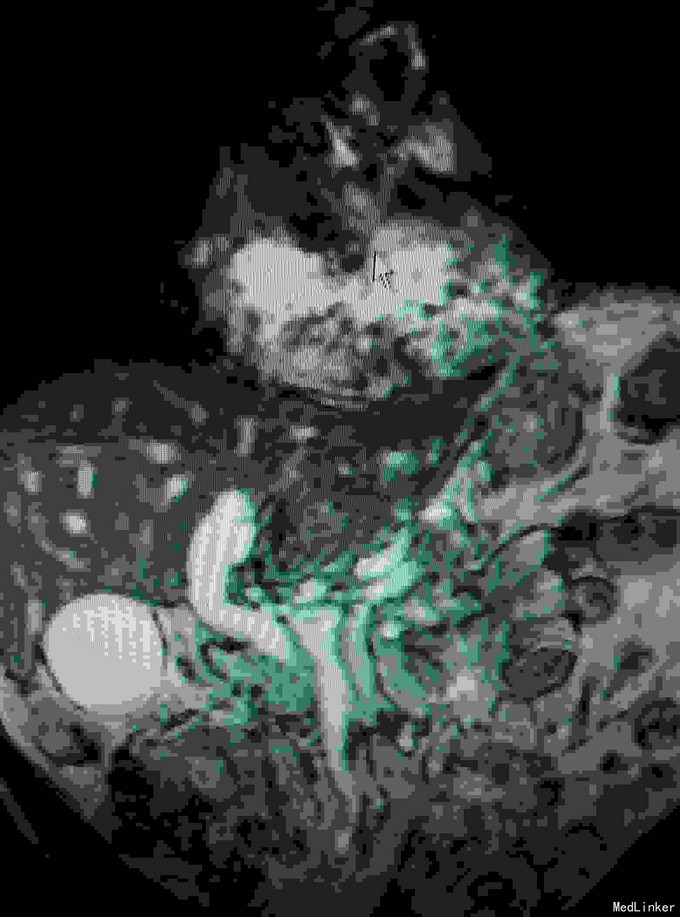

男患,74岁“发现全身皮肤及黏膜黄染2周”,2周前发现皮肤黄染,伴有纳差、厌油,无明显皮肤瘙痒,无发热、寒战,无恶心、呕吐,大便稍稀,无明显白陶土样大便,小便颜色基本正常。

全身皮肤黄染,虹膜黄染,心肺未见异常,腹部稍膨隆,肝区轻度扣击痛,Murphy症阴性。腹部查体腹部B超提示:肝内外胆管扩张,胆囊结石,胆总管下端可见低回声团。MRI如下:

梗阻性黄疸,择日进行了“胆囊切除,胆肠吻合术”,术中见胆囊及上段胆总管明显扩张,下段胆总管塌陷。